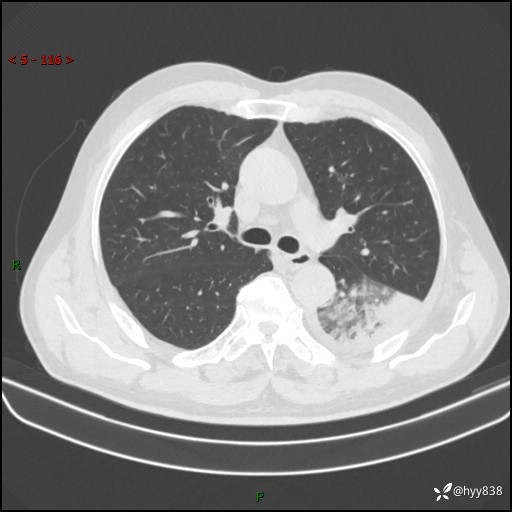

59岁/男,发热伴咳嗽3天。白班偶遇,“大叶性肺炎”,病原体挑战---结果公布~

【患者信息】:59岁/男

【主诉】:发热伴咳嗽3天

【现病史及既往史】:患者3天前无明显诱因出现发热,体温最高达38.6℃,伴有咳嗽,干咳为主,感乏力、肌肉酸痛,无明显头晕头痛、鼻塞、流涕、呼吸困难、胸痛、恶心呕吐、腹痛腹泻、尿频尿急等不适,于当地诊所输液治疗3天感症状无好转,仍有间断发热、咳嗽,现为求进一步诊治,于我院门诊就诊,门诊以“发热待查”收入我科进一步诊治。 患者自发病以来,精神、饮食、睡眠欠佳,大小便正常,体力、体重无明显变化。

【检查】:胸部CT平扫